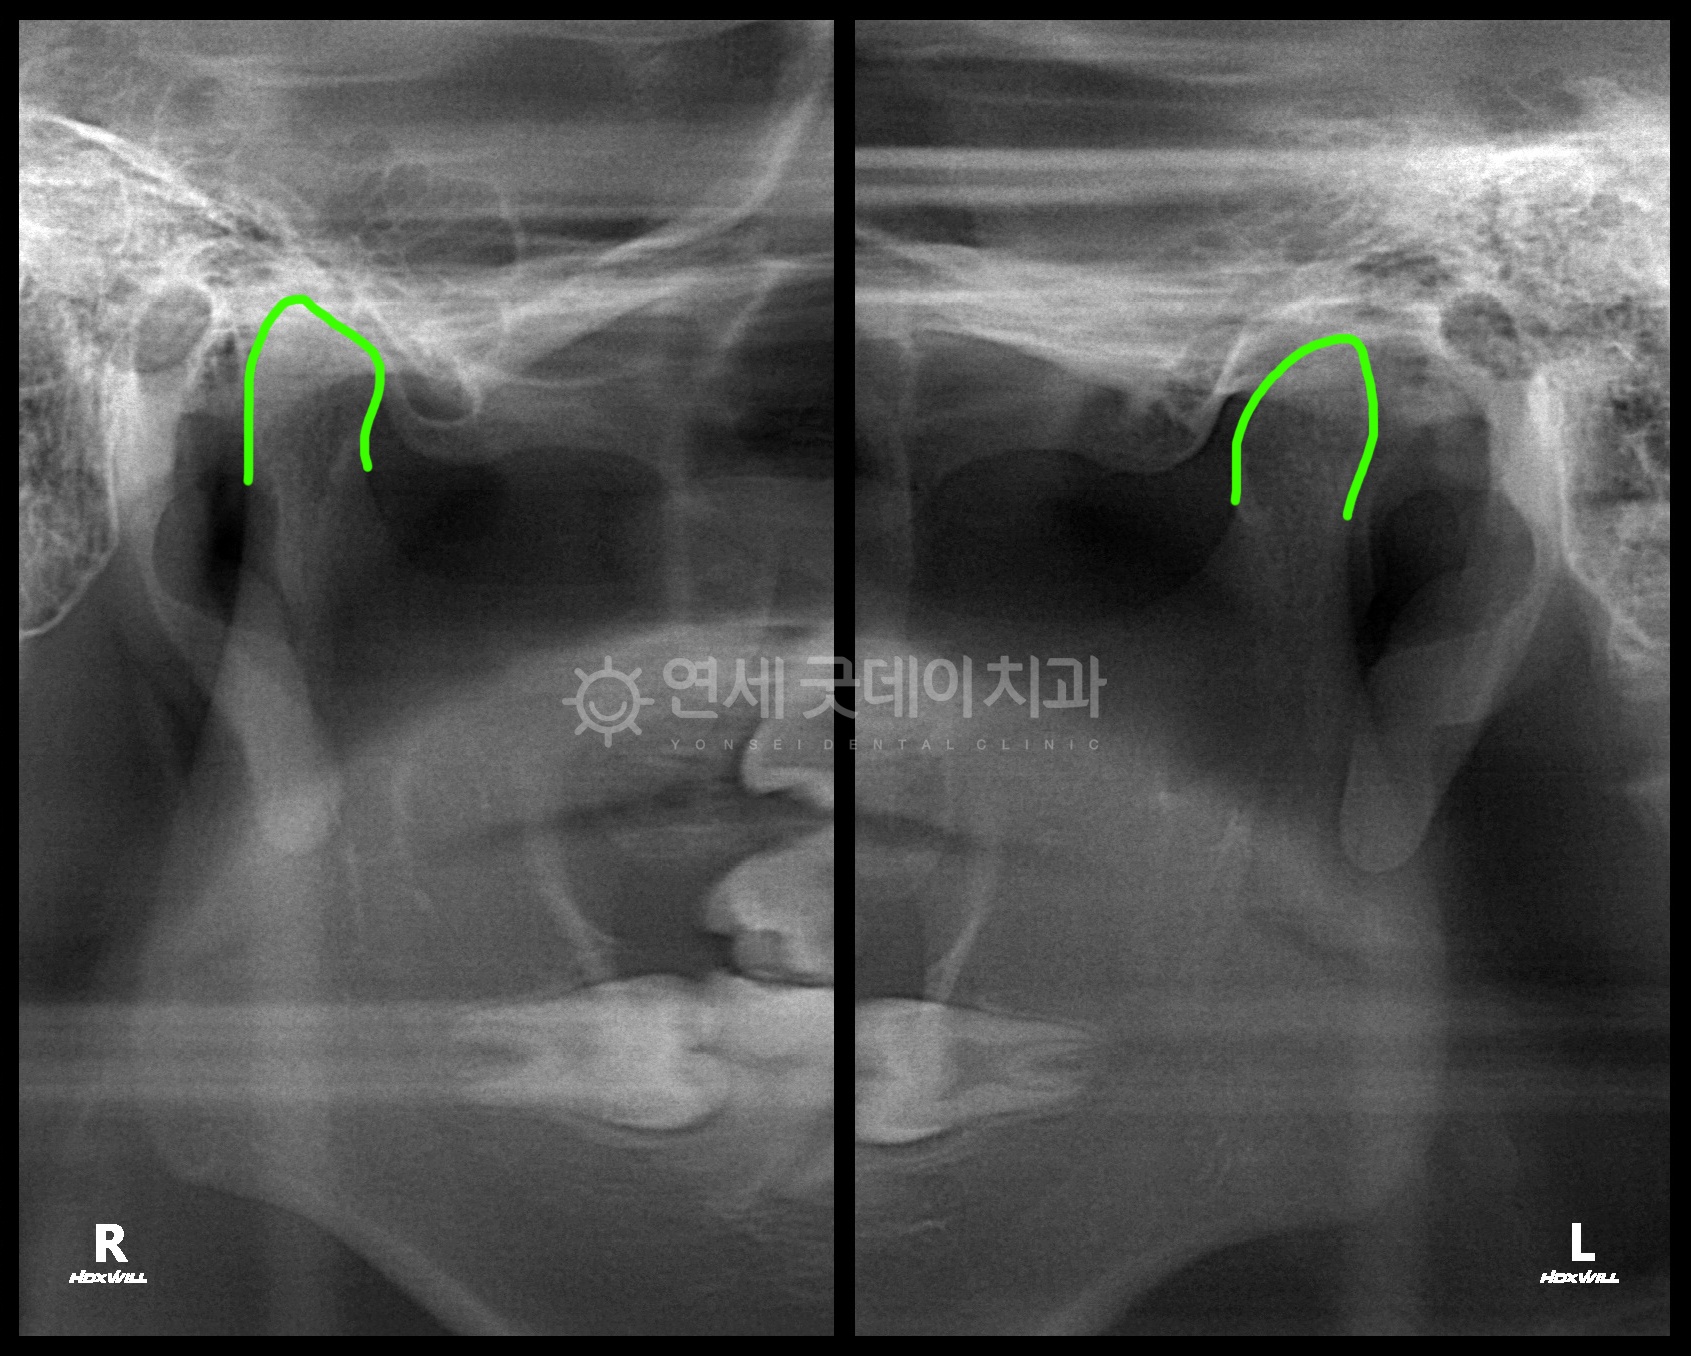

개방교합 턱관절교정 치료전후 – 트랙션 유지

턱관절교정을 주소로 내원해주신 20대 여성 환자분이십니다.

편안하게 물었을 때 어금니만 교합되고, 앞니가 뜨는 개방교합이 관찰됩니다.

턱관절의 퇴행성관절염은 10대 중후반~ 20대 초반의 여성에게 많이 나타납니다.

환자분은 과거 턱관절 디스크탈출증으로 인해

퇴행성관절염은 멈춘 상태였으나 턱이 많이 불안정하여

약 7개월 간의 스플린트 치료로 턱관절이 편안한 위치로 이동하면서

턱관절교정 후에는 개방교합을 개선하고 완전한 교합을 위해 비발치 인비절라인 교정 진행했습니다.

최근 약 2년 간의 인비절라인 교정을 마치셨습니다.

▲ 턱관절교정 치료전후 비교